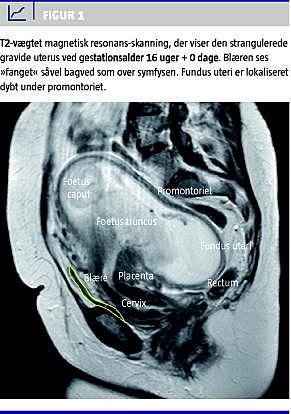

Patienten blev observeret under indlæggelsen, og blæren blev tømt vha. steril intermitterende kateterisering. Efter to døgns indlæggelse var der fortsat ingen spontan vandladning. Ved en magnetisk resonans (MR)-skanning bekræftedes diagnosen stranguleret retroflekteret uterus (Figur 1 ), og man fandt flere intramurale uterusfibromer, hvoraf den største målte 6 cm i diameter.